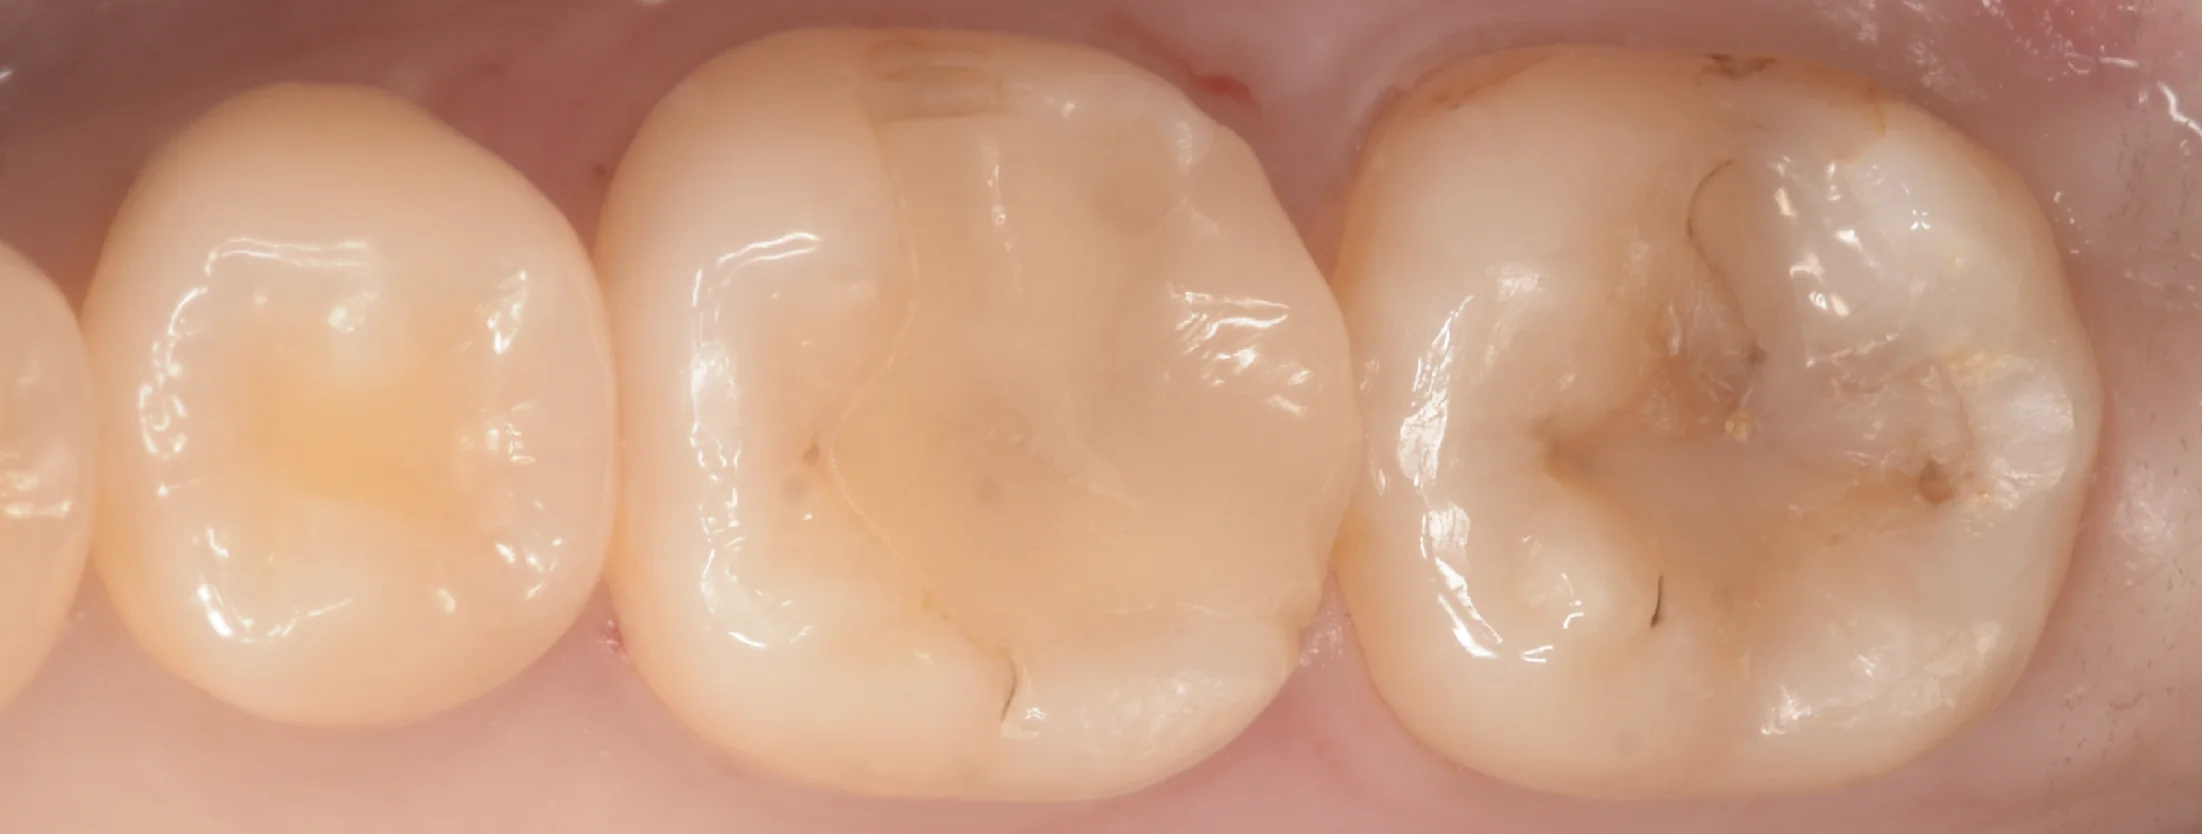

虫歯を取り切ったのがこちらになります。

むし歯除去時

歯茎よりも深いところまでむし歯になっていたのもありますが、それ以上に適合自体が悪かったのか歯茎に炎症があり、出血していますね。

そこ以外をみてもらうとわかりますが、この方は歯ブラシは非常に上手で歯肉にほぼ炎症は存在していません。

にも関わらずそこに炎症が出てしまっているのはやはりそういうことだと思われます。